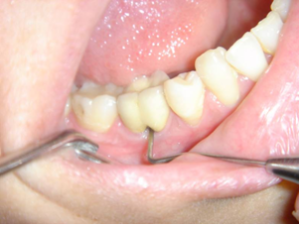

Nettoyage inter-radiculaire.

Une espace entre les deux racines est laissé accessible pour le passage d'une brossette inter-dentaire.

Une espace entre les deux racines est laissé accessible pour le passage d’une brossette inter-dentaire.

Le résultat 5 ans après est toujours excellent.